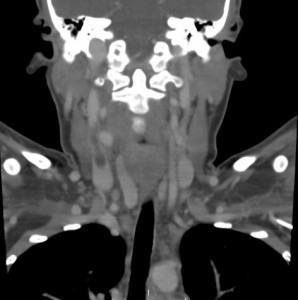

Jugular vein thrombosis is not common. It may occur in the internal or in the external jugular vein. Usually, a clot in the internal jugular vein is either the result of a procedure, or extension of clots in the arm veins.

The prevalence of upper extremity DVT is about 10% of all deep vein thrombosis and the prevalence of internal jugular vein thrombosis is perhaps a fraction of those.

As mentioned above, most of these clots will occur in hospitalized patients after someone tried to place a central line. In one series, most IJ clots were indeed iatrogenic, and occurred in-hospital, most commonly in association with central venous catheters.

The clinical manifestations include local neck pain and swelling. The swelling may also be apparent in the upper extremity. Sometimes, we can also see distension of the lower neck and upper chest veins (Urschel sign).

We should think of an internal jugular vein thrombus as we do of a deep venous thrombosis. While lower than in the lower extremities, the prevalence of short and long-term complications is not negligible. The most grave consequences include pulmonary embolism which may occur as much as 10.3% of cases. Another potential complication is post-thrombotic syndrome. Other consequences include thrombus propagation, and recurrent events.